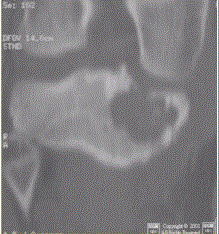

患者男,15岁。右膝X线平片和CT检查见下图。病变发生部位是A.骨端B.干骺端C.骨骺D.骨干E.关节腔

问题 患者男,15岁。右膝X线平片和CT检查见下图。 病变发生部位是

选项 A.骨端 B.干骺端 C.骨骺 D.骨干 E.关节腔

答案 C